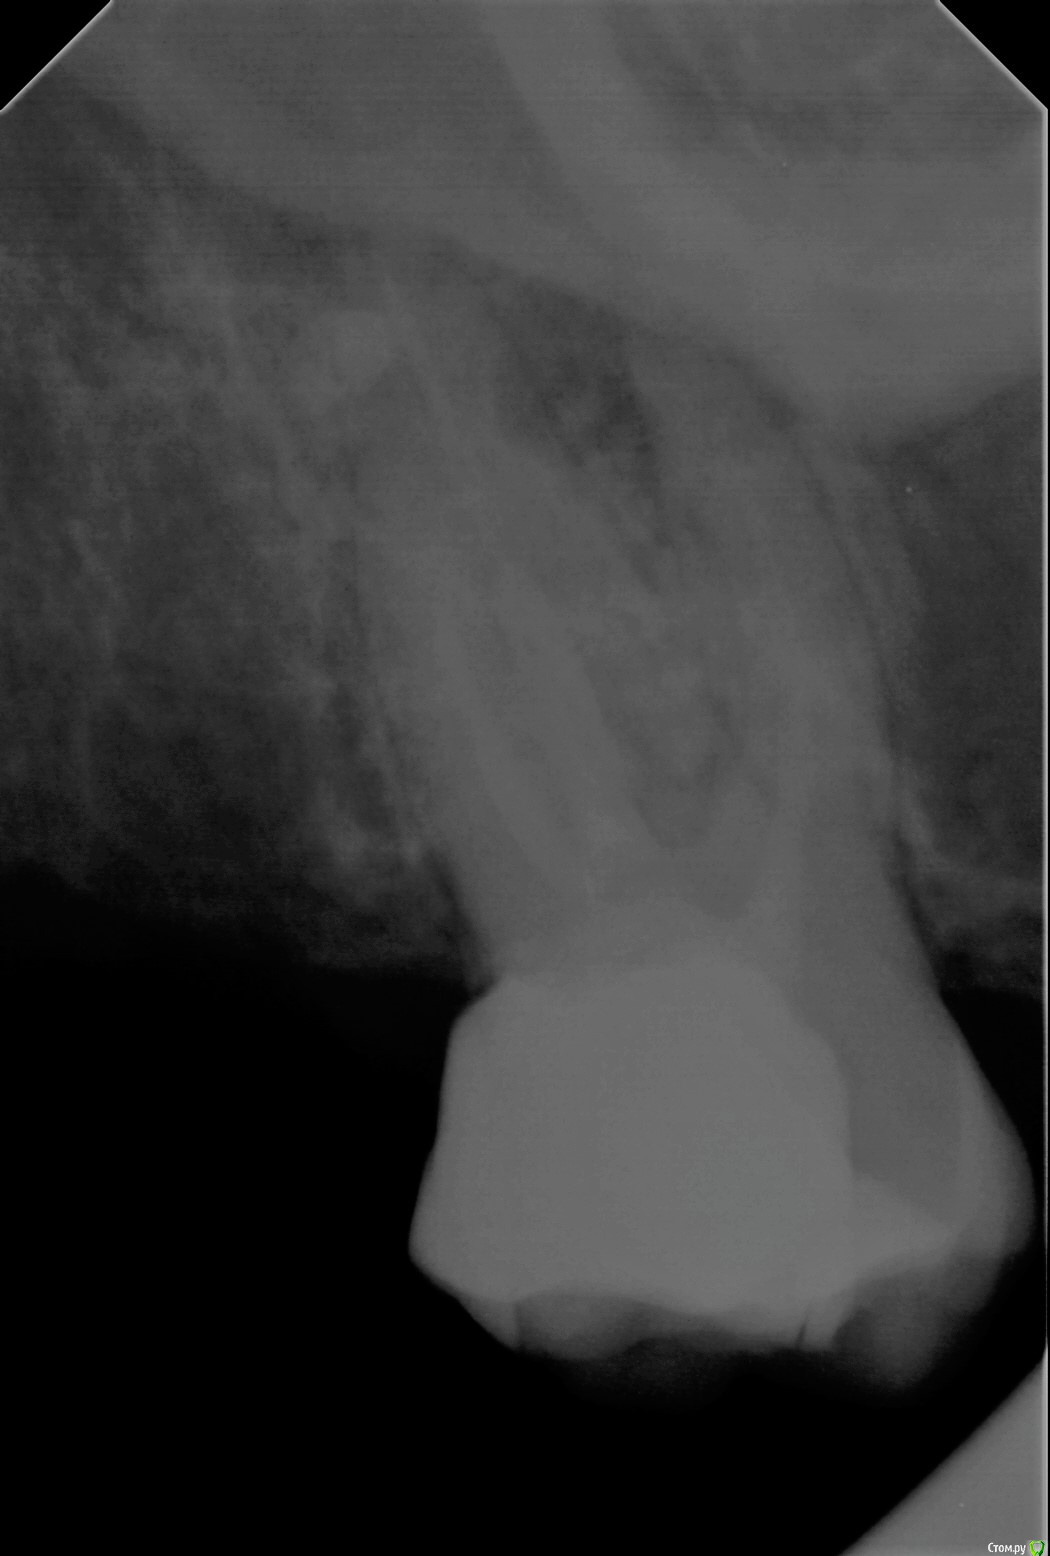

Wedernikoff Опубликовано 5 октября, 2017 Автор Поделиться Опубликовано 5 октября, 2017 Доброе утро. Вопрос возник потому, что мне врачи сказали, что там "огромная кистогранулёма" (это цитата). И зуб можно попробовать спасти только у очень опытного микроскописта без гарантии. Не болит, начала потихоньку крошиться пломба. Спасибо Вам за отклик. Отличного дня Ссылка на комментарий

red_butler Опубликовано 5 октября, 2017 Поделиться Опубликовано 5 октября, 2017 качество представленного снимка не позволяет его интерпретировать, сделайте Кт Ссылка на комментарий

Wedernikoff Опубликовано 5 октября, 2017 Автор Поделиться Опубликовано 5 октября, 2017 Есть более отчётливый снимок, но формат его TIF не выложился тут. Я сейчас попробую поменять формат и выложить его тут. Там всё видно. Спасибо Ссылка на комментарий

Wedernikoff Опубликовано 5 октября, 2017 Автор Поделиться Опубликовано 5 октября, 2017 Быть может, по этому снимку будет видно нормально. Ссылка на комментарий

St. Опубликовано 5 октября, 2017 Поделиться Опубликовано 5 октября, 2017 Да, воспаление на корнях действительно присутствует. Метод лечения это перелечивание каналов, на которое и правда не может быть гарантии в принципе. После перелечивания нужно накрыть зуб коронкой Ссылка на комментарий